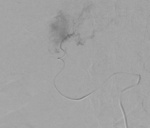

– Metoda, którą stosujemy od ubiegłego roku, polega na tym, że poprzez specjalny cewnik wprowadzony do tętnicy udowej docieramy do wątroby, a następnie do każdej zmiany przerzutowej i bezpośrednio do niej podajemy chemioterapeutyk, jednocześnie zamykając naczynie i odcinając dopływ krwi do guza i tym samym jego odżywianie (ryc. 1, 2) – mówi prof. dr hab. med. Aleksander Falkowski z Zakładu Radiologii Zabiegowej szczecińskiego szpitala.